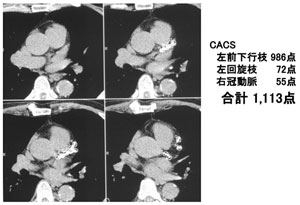

経過:胸部X 線では特記する異常所見なく、胸 部CT でも肺野には特記所見なかったが、図1 に示すように高度の冠動脈石灰化を認めた。 CACS(算出法は後述)1,113 点であった。運 動負荷心筋シンチを実施したところ、心電図に は有意な心電図変化がみられないにもかかわら ず、心筋イメージでは前壁後壁に虚血を認めた。 心臓カテーテル検査を実施したところ、図2 に 示すように左主幹部病変を伴う重症冠動脈疾患 と判明し、冠動脈バイパス術を実施した。無症 候性の虚血性心疾患をスクリーニングできる CACS の威力を初めて認識した一例であった。

図1

図1 症例:胸部CT